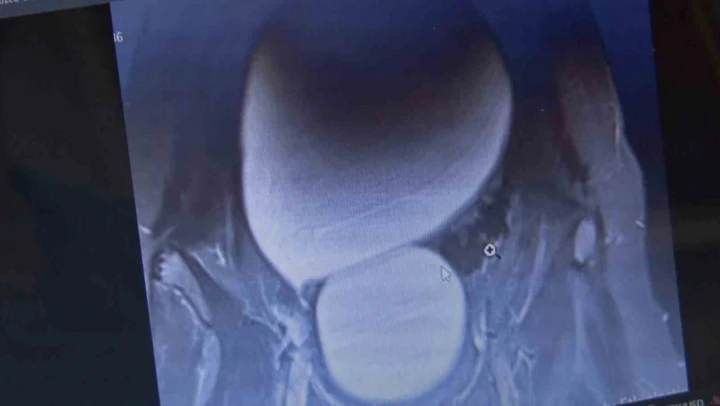

Sivas'ta yaşayan 12 yaşındaki N.B. şiddetli karın ağrıları ve düzensiz adet kanamaları şikayetiyle hastaneye başvurdu. Yapılan detaylı tetkikler sonucunda genç kızın karın bölgesinde yaklaşık 25 santimetre çapında adeta kavun büyüklüğünde bir kist olduğu tespit edildi. Medicana Sivas Hastanesi'nde Çocuk Cerrahisi Uzmanı Op. Dr. Mahmut Aluç tarafından gerçekleştirilen başarılı bir operasyonla, genç kızın sol yumurtalığında bulunan ve karaciğere kadar uzanan devasa kist içerisindeki 1.6 litre su boşaltılıp, başarıyla çıkarıldı. Sağlığına kavuşan genç kız taburcu edildi.

Çocuk Cerrahisi Uzmanı Op. Dr. Mahmut Aluç, kisttin içerisinden yaklaşık 1.6 litre sıvı boşaltıldığını söyleyerek, ' Karın ağrısı, düzensiz adet şikayetiyle bize geldi. Dışarıda yapan tetkiklerde ve bizde yapılan tetkiklerinde karın içerisinde yaklaşık yirmi beş santimetrelik çapında bir kitli kitle tespit ettik. Burada da tetkiklerimize tekrar baktığımızda sol över kökenli bir kisttik yapı olduğunun farkına vardık. Gerekli incelemeleri yaptıktan sonra ve ailenin onayını aldıktan sonra hastayı operasyona aldık. Karaciğere kadar uzanan bir kisttik yapımız vardı. Onun içerisinde yaklaşık 1.6 litre sıvı boşalttık. Over dokusunu, yumurtalık dokusunu koruyarak kisti tamamen eksize ettik. Hastamızı şifayla taburcu ettik. Patoloji sonucumuz da iyi huylu olarak geldi' dedi.